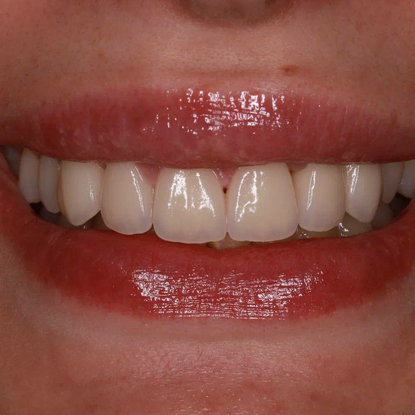

Лечение контактного кариеса на фронтальных зубах

Оказанные услуги

Лечение

Лечение контактного кариеса на двух передних зубах с дальнейшей постановкой пломбы и ее полированием до блеска

Результат

Красивая широкая улыбка без потемнений между зубов

Лечащий врач

Монеткина Валерия Алексеевна